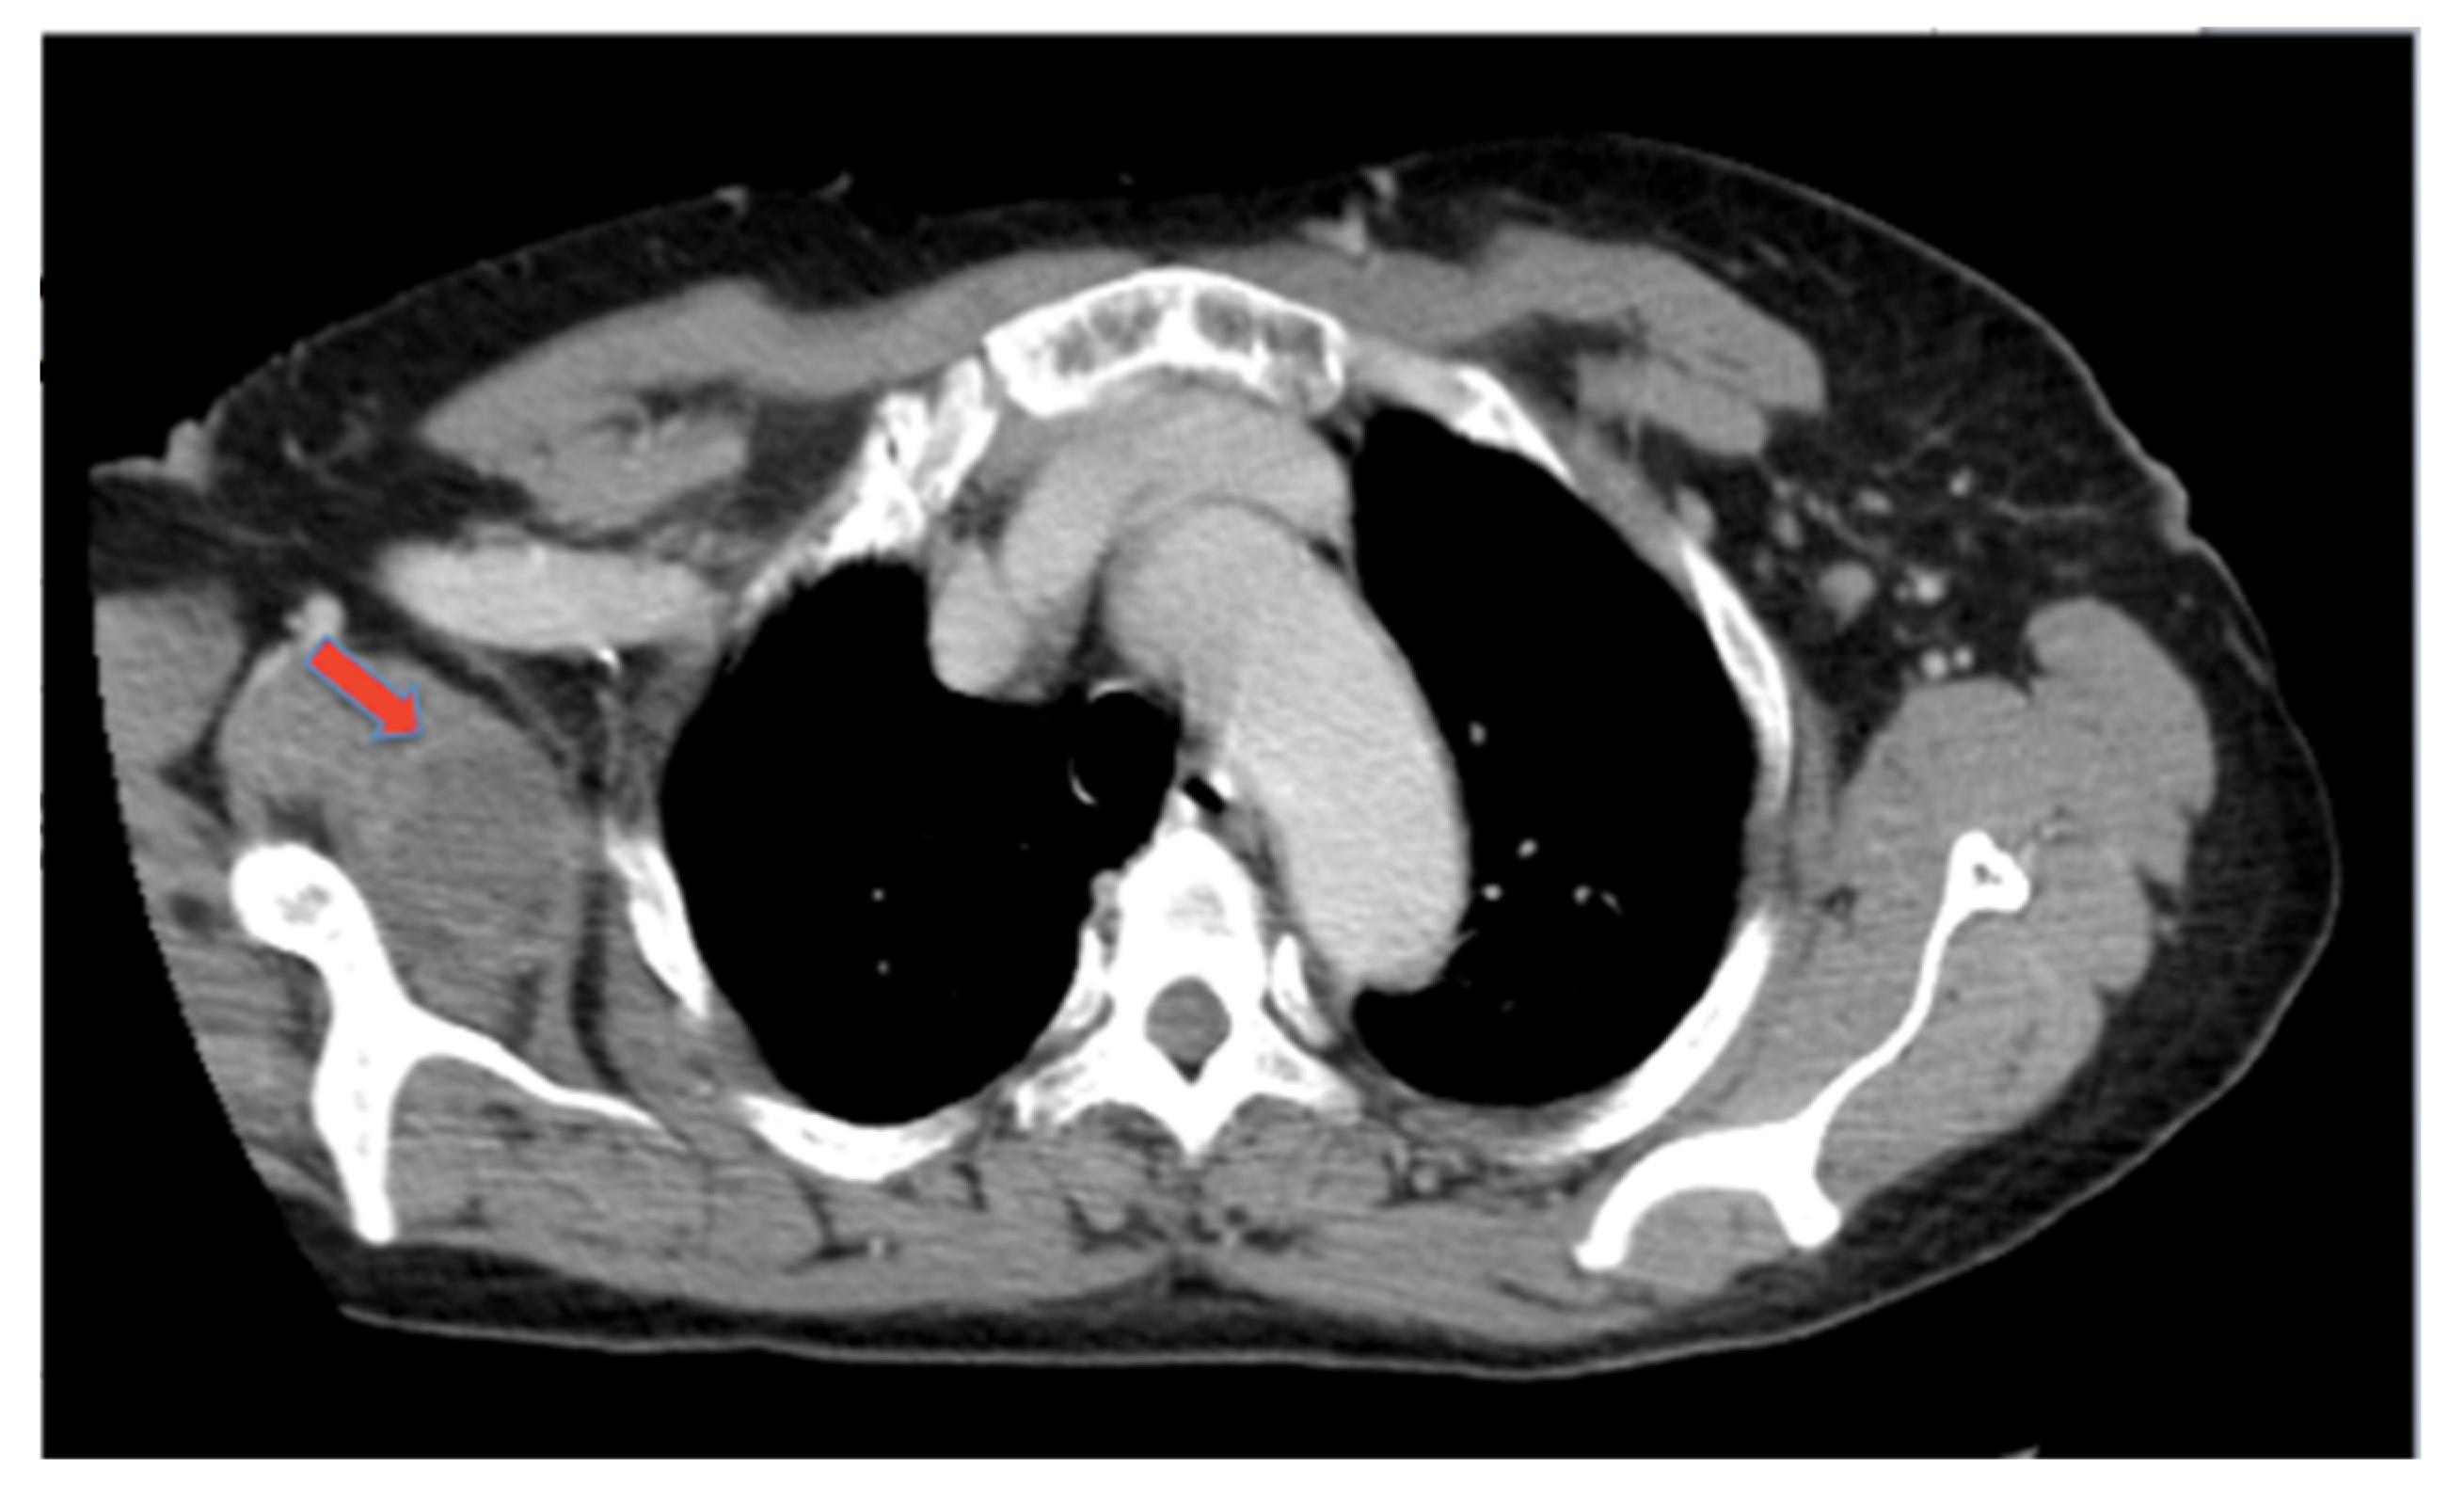

2. Discussion